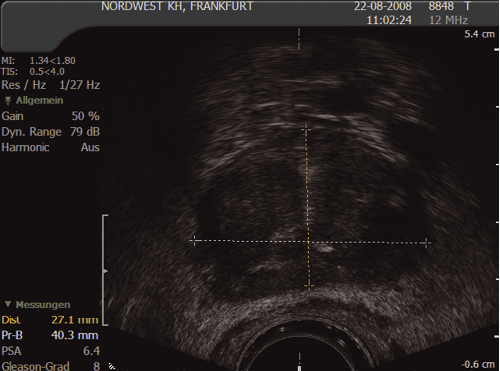

6.5 Prostate measurement

It is routine to measure the prostate volume (in g/ml)), which may be important in offering treatment options. The prostate is measured in three planes:

In the transverse view: anterior to posterior (width) (1) and height (2); and in the longitudinal plane from the bladder neck to the apex (length) (3). This can be calculated using the formula:

Ω/6 × height × width × length (in cm) (Ω/6 may be substituted by 0.51)

Most ultrasound machines will automatically calculate the volume.

Fig. 12. Prostate measurement – transverse view

(Courtesy: S. Hieronymi)